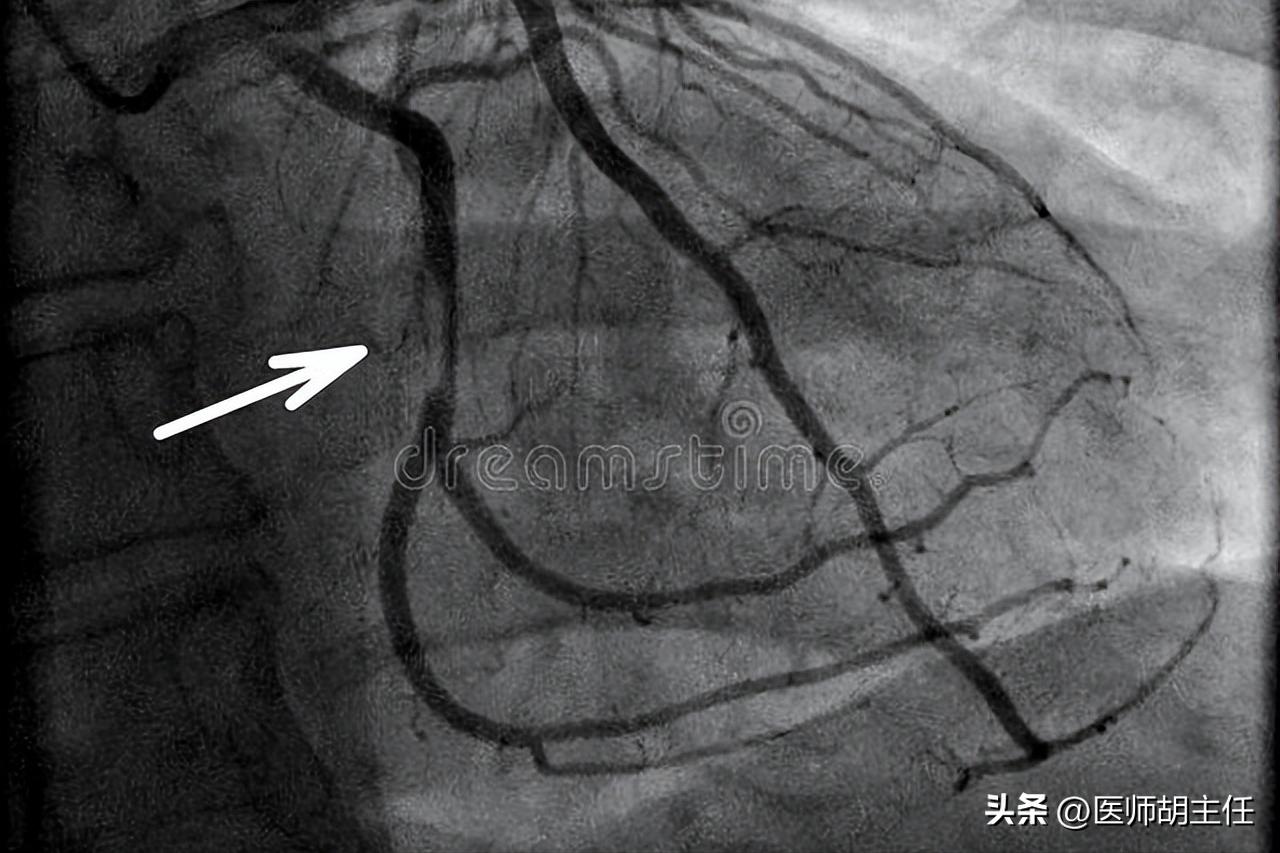

冠脉造影是一种有创的冠脉介入性检查方法。是临床用于诊断冠状动脉粥样硬化性心脏病的“金标准”。

冠状动脉的主要操作方法为,用特殊的导管找到下肢股动脉或者上肢桡动脉然后刺入,再沿着主动脉上行找到冠状动脉,将造影剂注入就会使左右冠脉在X光下显影,这样就可以判断冠状动脉有无斑块、狭窄、堵塞以及堵塞的面积,以此来确定病灶以及手术方案(支架或者搭桥等),支架手术多是在造影的同时进行,在造影的整个过程中患者保持平躺的体位,造影的创口非常小,仅为一个小出血点,按压便能止血。